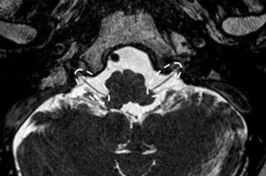

A Steady-state free precession (SSFP) axial image showing the optic nerves (arrows).

A Steady-state free precession (SSFP) axial image showing the oculomotor nerves (arrows).

A Steady-state free precession (SSFP) axial image showing the trochlear nerves (arrows).

A Steady-state free precession (SSFP) axial image showing the abducens nerves (circles).

A Steady-state free precession (SSFP) axial image showing the facial nerves (dotted arrows).